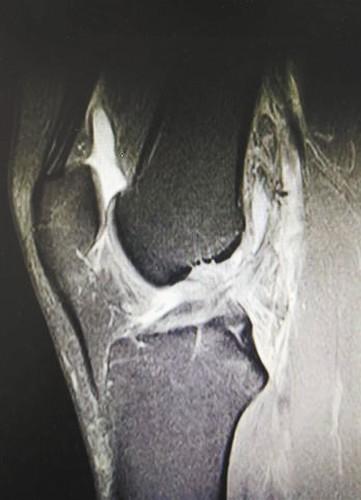

医生为小李进行了详细的检查后,诊断为左膝关节前交叉韧带断裂、半月板撕裂,并通过关节镜微创手术,在其左膝关节周围开了两个0.5厘米和一个3厘米的小口,即完成了前交叉韧带重建和半月板缝合术。术后第2天,小李就可以拄着拐杖下地了。